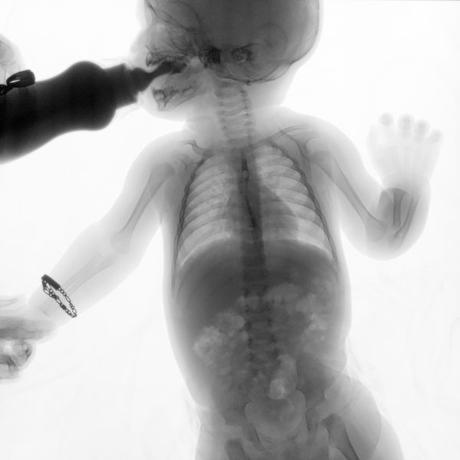

ESTUDIO SOLICITADO: SERIE ESOFAGOGASTRODUODENAL.

Se realiza Esofagograma con material de contraste baritado, por vía oral y por medio de control fluoroscópico se toman distintas proyecciones observando lo siguiente.

Se observa mecánica de la deglución con adecuado paso de medio de contraste de faringe a esófago sin presencia de defectos de llenado depósitos anómalos o fuga del mismo.

ESÓFAGO se observa de situación, calibre y trayecto normal. Contornos regulares y bien definidos. No se observan depósitos anómalos, defectos de llenado o fuga del medio de contraste.

UNION ESOFAGOGASTRICA se observa con calibre y situación normal. Sin observar reflujo a las maniobras de valsalva

ESTOMAGO se observa en su situación habitual, distendido, sin defectos de llenado.

- Actualmente no se demuestra Reflujo gastro-esofágico.

- Estudio de apariencia normal.